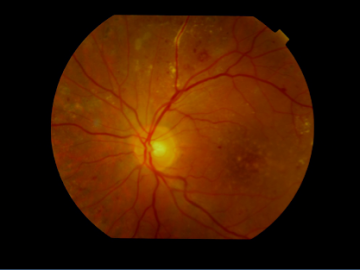

Figure 1: Diabetic retinopathy

Diabetic retinopathy is the medical name for diabetic retinal disease. Diabetic retinopathy is the main cause of vision loss among working-age adults. In diabetic retinopathy, retinal blood vessels are damaged and begin to leak fluid or blood.

Typically, diabetic retinopathy doesn’t cause sudden vision loss. Vision levels are usually fine at the onset of the disease. This is when the disease should be diagnosed and treated. Those patients diagnosed at the advanced stages usually end up with low vision.